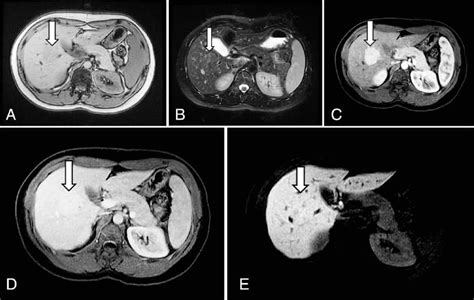

So, how do doctors figure out if you have FNH? It’s all about the imaging, my friends! As we touched upon, FNH has some pretty distinct features on scans like MRI and CT. The central scar is a big one. It’s usually bright on certain MRI sequences, which helps doctors differentiate it from other liver lesions. Also, FNH tends to enhance (light up) in a specific way after contrast dye is injected. It gets a lot of blood flow from an artery, so it lights up brightly in the early arterial phase of the scan and then gradually fades. This pattern of enhancement is super characteristic. Doctors also look at the overall shape and borders of the lesion. FNH lesions are usually well-defined and don’t invade nearby structures. Now, here’s where Kupffer cells come into play indirectly. Some advanced MRI techniques, like using specific contrast agents that are taken up by Kupffer cells (called hepatobiliary contrast agents), can further help in the diagnosis. In FNH, the Kupffer cells might not be functioning or present in the same way as in the normal liver tissue. So, how these contrast agents behave can give doctors even more clues. If the lesion takes up the contrast agent normally, it suggests it’s made of well-functioning liver cells, which is typical for FNH. If it doesn’t take up the contrast, it might point towards a different type of lesion. This level of detail in imaging is what allows radiologists to be so confident in diagnosing FNH, distinguishing it from other, potentially more serious, liver conditions. It’s a sophisticated dance of light and shadow on the scans, all interpreted by highly trained eyes. The accuracy of these imaging techniques has significantly improved over the years, reducing the need for invasive biopsies in many cases. However, if the imaging is ambiguous, a biopsy might still be considered, but it’s generally a last resort for FNH diagnosis. The goal is always to achieve a confident, non-invasive diagnosis whenever possible.